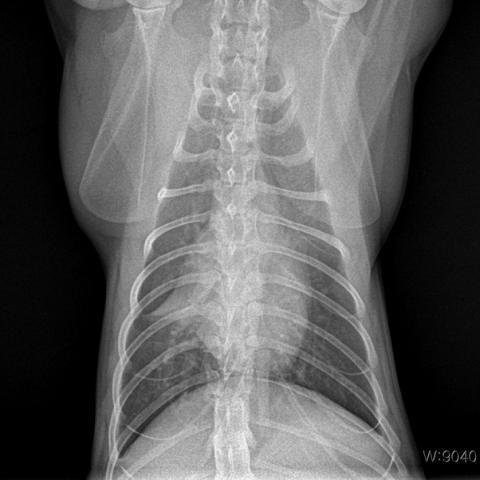

°í¾çÀÌÀü¿°¼ºº¹¸·¿°

(Feline Infectious Peritonitis)

°í¾çÀÌÀü¿°¼ºº¹¸·¿°Àº °í¾çÀÌÄڷγª¹ÙÀÌ·¯½º°¡ ¿øÀÎü·Î, °í¾çÀÌ Ã¼³»¿¡ Àẹ »óÅ¿´´ø Äڷγª¹ÙÀÌ·¯½º°¡ ¸Íµ¶¼ºÀ» °¡Áø ¹ÙÀÌ·¯½º·Î º¯À̵Ǿî Àü½Å Àå±â¿¡ ¿°ÁõÀ» ÀÏÀ¸Å°°í, ºóÇ÷, Ȳ´Þ, Èä¼ö, º¹¼ö, ½Å°æ Áõ»óÀ» ÀÏÀ¸Å°´Â Àü¿°¼º ÁúȯÀÔ´Ï´Ù. Àü¿°¼ºº¹¸·¿°Àº ÀÓ»ó Áõ»ó, Ç÷¾× °Ë»ç, Èä/º¹¼ö PCR °Ë»ç, ¹æ»ç¼±, ÃÊÀ½ÆÄ, CT¸¦ ºñ·ÔÇÑ ¿µ»ó °Ë»ç °á°ú¸¦ Á¾ÇÕÀûÀ¸·Î ÆÇ´ÜÇÏ¿© Áø´ÜÇÏ°Ô µË´Ï´Ù. ÀÏ´Ü È®ÁøÀÌ µÇ¸é Ç×¹ÙÀÌ·¯½ºÁ¦¸¦ Åõ¿©ÇÏ´Â °Í¸¸ÀÌ À¯ÀÏÇÑ Ä¡·á ¹æ¹ýÀÔ´Ï´Ù.

±¹³»¿Ü ´Ù¼öÀÇ ¿¬±¸ °á°ú¸¦ ÅëÇØ ÃʱâÀÇ Àü¿°¼ºº¹¸·¿°ÀÇ °æ¿ì Ç×¹ÙÀÌ·¯½ºÁ¦¸¦ Åõ¿©ÇÏ¿´À» ¶§ Ä¡·á È¿°ú°¡ ¸Å¿ì ¶Ù¾î³­ °ÍÀ¸·Î ¹àÇôÁö°í ÀÖ½À´Ï´Ù. ´Ù¸¸, Áúȯ ¸»±â¿¡ À̸£·¯ ½Å°æ Áõ»óÀÌ µ¿¹ÝµÈ »óÅÂÀ̰ųª, ȯ¹¦°¡ ±âÀú ÁúȯÀÌ ÀÖ´Â °æ¿ì, ³ë·É¹¦ÀÇ °æ¿ì¿¡´Â Ç×¹ÙÀÌ·¯½ºÁ¦ Åõ¿© ½Ã Ä¡·á ¹ÝÀÀÀÌ ÁÁÁö ¾ÊÀº ÆíÀÔ´Ï´Ù.

½É°¢ÇÑ ºóÇ÷·Î ¼öÇ÷ÀÌ ÇÊ¿äÇϰųª ½Ä¿å ÀýÆó, ±â·Â ÀúÇÏ µîÀ¸·Î ¼ö¾× óġ°¡ ÇÊ¿äÇÑ »óȲÀ̸é ȯ¹¦ÀÇ »óŸ¦ ¾ÈÁ¤½Ã۱â À§ÇØ ÀÔ¿ø Ä¡·áÇØ¾ß ÇÒ ¼öµµ ÀÖ½À´Ï´Ù. ±×·¯³ª ³¸¼± ȯ°æÀÌ ÁÖ´Â ½ºÆ®·¹½º°¡ ÁúȯÀ» ´õ ¾ÇÈ­½Ãų ¼ö ÀÖ¾î °¡´ÉÇϸé Åë¿ø Ä¡·á¸¦ ±ÇÀ¯ µå¸³´Ï´Ù.